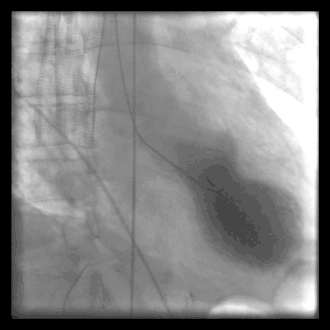

A common example of cardiac catheterization is coronary catheterization that involves catheterization of the coronary arteries for coronary artery disease and myocardial infarctions ("heart attacks"). Catheterization is most often performed in special laboratories with fluoroscopy and highly maneuverable tables. These "cath labs" are often equipped with cabinets of catheters, stents, balloons, etc. of various sizes to increase efficiency. Monitors show the fluoroscopy imaging, electrocardiogram (ECG), pressure waves, and more.

Coronary angiography is a diagnostic procedure that allows visualization of the coronary vessels. Fluoroscopy is used to visualize the lumens of the arteries as a 2-D projection. Should these arteries show narrowing or blockage, then techniques exist to open these arteries. Percutaneous coronary intervention is a blanket term that involves the use of mechanical stents, balloons, etc. to increase blood flow to previously blocked (or occluded) vessels.